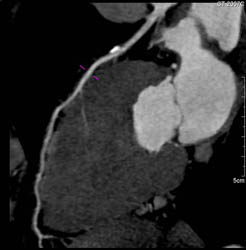

Diseased LAD